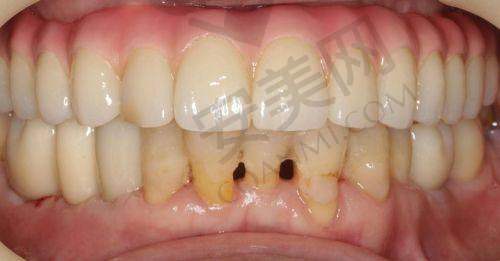

许多在汕头天佑口腔接受韩国维钛种植牙手术的患者都给出了积极的反馈。他们表示,从术前的询问到术后的复查,整个过程都感受到了医院的专精和贴心服务。在手术过程中,蔡万兴医生的不错技术让他们没有感到太多的痛苦,而且术后修复也比较顺利。一位患者说:“我之前一直担心种植牙手术会特别疼,但是在汕头天佑口腔,蔡医生的操作非常熟练,手术特别快就完成了,现在我的牙齿修复得良好,咀嚼功能也和以前一样,真的特别感谢他们。”还有患者提到,医院的环境和服务态度让他们在就诊过程中感到特别舒适,就像在家一样放松。